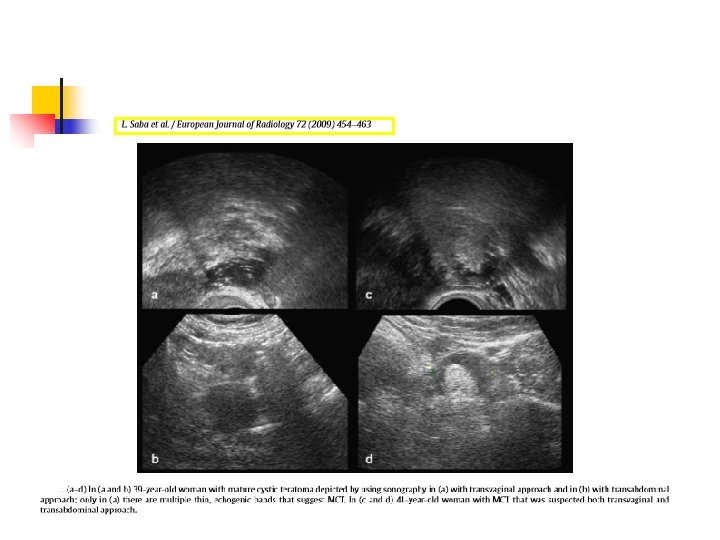

Beklentisel yaklaşım-usg USG belirleyiciliği %59 -%94. Uysal 2014, Tongson 2008 Dermoid kistin en önemli özelliği fokal yada diffuz akustik gölge veren yüksek ekolu kitledir. PPD %80. Peter 1998 İmmatür teratomda ise heterojen yapı içinde dağınık kalsifikasyonlara sahip, geniş solid alanlar içeren büyük kitleler mevcuttur. Outwater 2001 CT ve MR’ın usg den daha yüksek belirleyicilik oranı vardır. Saba 2009

usg Karakteristik USG bulgusu kistik uniloküler kitle ve içerisinde dens ekojenik tüberkül( Rokitasky nodülü yada dermoid plak) olmasıdır. Multani 2015, Saba 2009

Zupi 2003 Tongsong 2008

Tongsong 2008

Tongsong 2008 Zupi 2003